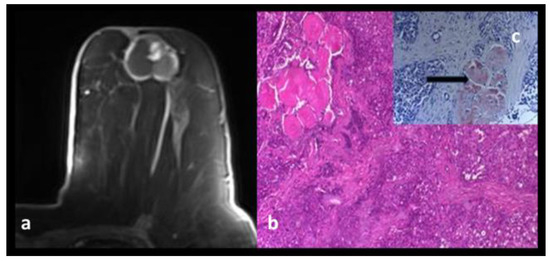

Idiopathic Granulomatous Mastitis

Breast Abscesses

Diabetic Mastopathy